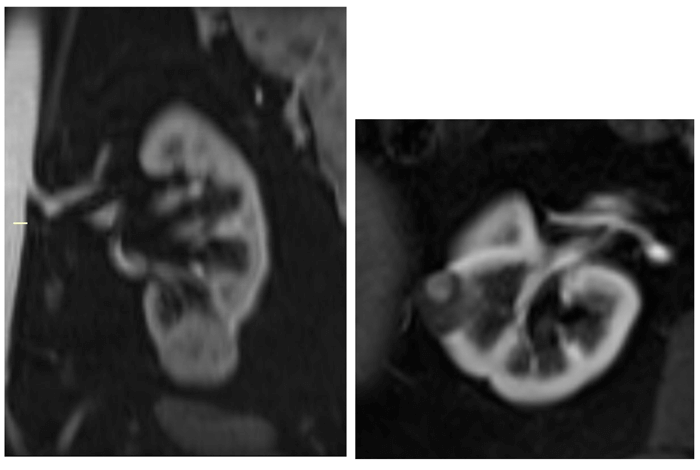

Papillary RCC is often hypointense on T2-weighted sequences and demonstrates low-level homogenous contrast enhancement (Figure 10). Clear cell RCC on the other hand appears hyperintense on T2-weighted sequences with intense heterogenous contrast enhancement and early wash-out.

Figure 10: Type I papillary RCC demonstrating quite low-level homogenous enhancement (left).

Bosniak IV cystic lesion within the contralateral kidney (right) also excised revealing papillary RCC.